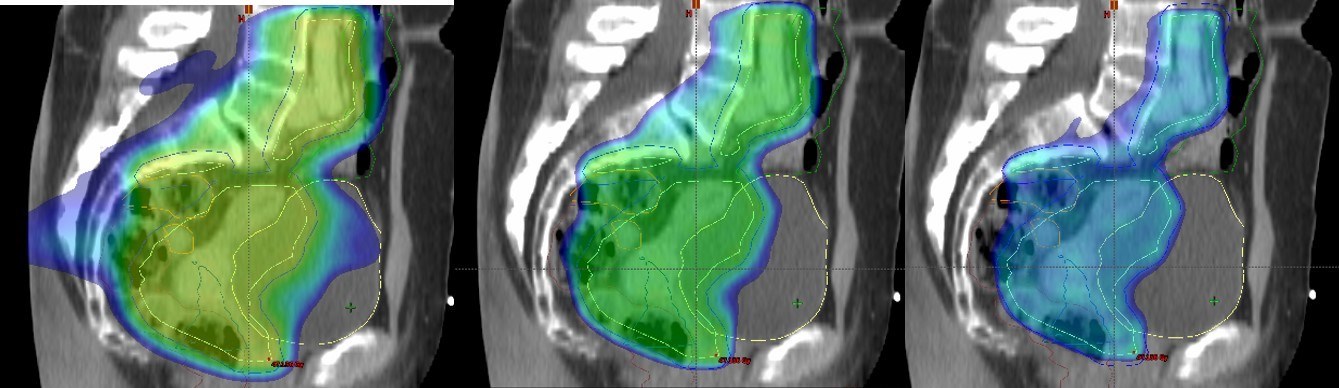

Project 4: Proton therapy in gynaecological cancer

Proton therapy can reduce the irradiation of normal tissue in pelvic radiotherapy. In particular, there is potential to spare exposure of bowel and bladder in post-operative cervix cancer patients